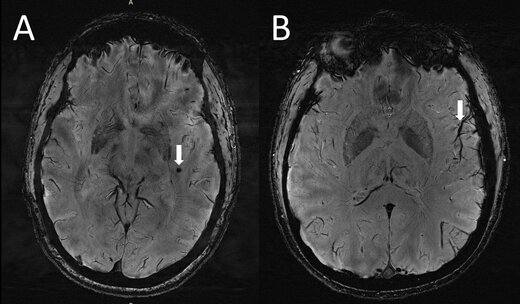

ژو و همکارانش، به دنبال آن هستند تا ارتباط میان میگرن وبزرگ شدن فضاهای اطراف عروقی را درک کند. این محققان با بهرهگیری از MRI ۷T با وضوح فوقالعاده بالا، به مقایسه ساختاری تغییرات میکروواسکولار (رگهای خونی بسیار ریز) در انواع مختلف میگرن پرداختند. ژو در این رابطه گفت:« این اولین بررسی با استفاده از MRI با وضوح فوقالعاده بالاست که در آن به بررسی تغییرات میکرو واسکولار مغز در پی بروز میگرن، بهویژه در فضاهای اطراف عروقی پرداخته میشود. از آنجا که MRI ۷T قادر است تا تصاویری با وضوح و با کیفیت به مراتب بالاتری نسبت به دیگر دستگاههای MRI از مغز ارائه دهد، میتوان از این دستگاه برای تشخیص تغییرات جزئیتر و ریزتری که بعد از بروز میگرن در بافت مغز ایجاد میشود، بهره برد.»

محققان، در جریان این بررسی فضاهای بزرگ شده اطراف عروقی را در سنتروم سِمی اوال (بخش مرکزی ماده سفید مغز) و غدههای قاعدهای را اندازهگیری کردند. افزایش و شدت ماده سفید مغز (ضایعهای که در MRI به روشنی مشخص است) با بهرهگیری از مقایس Fazekas اندازهگیری شد. خونریزیهای میکروبلید مغزی (خونریزیهای بسیار ریز در مغز) با خونریزیهای میکروبلید در آناتومی بدن با مقیاس رتبهبندی، طبقهبندی شدند. محققان در عین حال دادههای بالینی افراد از جمله دوره بیماری و شدت آن، نشانهها و علائم در هنگام انجام اسکن و وجود هاله و منطقه سردرد فرد را نیز جمعآوری کردند.

تجزیه و تحلیلهای آماری حکایت از آن داشت که تعداد فضاهای بزرگ شده اطراف عروقی در مرکز سِمی اوال مغز افراد، در بیمارانی که میگرن داشتند، به مراتب بیشتر از افراد سالم بود. به علاوه کمیت فضاهای بزرگ شده اطراف عروقی در مرکز سِمی اوال با عمق ماده سفید، از نظر شدت جدی بودن در بیماران میگرنی در ارتباط است.

ژو ادامه داد:« ما در تحقیقات درباره میگرن مزمن و میگرن اپیزودیک بدون هاله به این نتیجه رسیدیم که در هر دو دسته افراد مبتلا به این نوع میگرنها، فضاهای اطراف عروقی در مرکز سِمی اوال بزرگتر بودند. اگرچه ما هیچ تغییر قابل توجهی در شدت ضایعات بخش سفید مغز در افراد مبتلا به میگرن و افراد بدون میگرن پیدا نکردیم، ولی این ضایعات بخش سفید مغز به طور قابل توجهی با وجود فضاهای بزرگ شده اطراف عروقی مرتبط بودند. این بدان معناست که تغییرات در فضای اطراف عروقی، ممکن است منجر به افزایش ضایعات بیشتری در بخش سفید مغز شوند.»